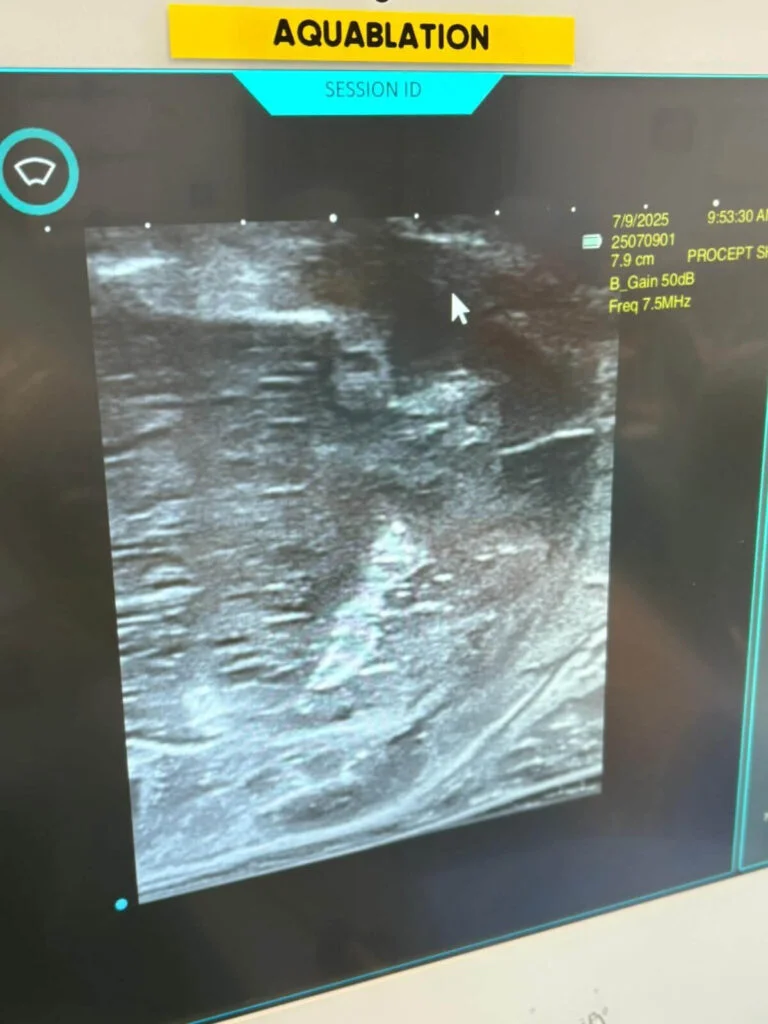

Aquablation therapy is an advanced surgical procedure that combines robotics, real-time imaging, and a heat-free waterjet to remove obstructive prostate tissue with high precision. Unlike traditional surgical approaches, the procedure does not use heat to ablate tissue, which can help preserve surrounding anatomy important for urinary and sexual function while delivering long-lasting symptom relief.

The treatment is performed under anaesthesia using an image-guided robotic system that maps the prostate and directs a high-velocity waterjet to resect only the excess tissue responsible for lower urinary tract symptoms (LUTS). Because Aquablation is delivered through the urethra, no external incisions are required, helping reduce recovery time and surgical trauma.